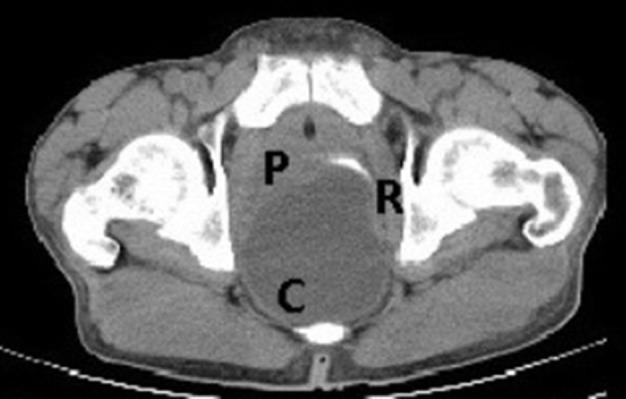

Tailgut duplication cyst (retro-rectal cystic hamartoma) is a rare congenital developmental lesion arising from post-natal primitive gut remnants. Tailgut cysts are found more commonly in middle-aged females. It may be asymptomatic or symptomatic in complicated cases. Major differentials include epidermoid cyst, dermoid cyst and anterior meningocele. Unfortunately no radiological sign can specifically diagnose it and surgical resection and histopathology remain the cornerstone for diagnosis. Here we present a case of symptomatic tailgut duplication cyst in an adult male.

尾肠重复囊肿(直肠后囊性错构瘤)是一种罕见的先天性发育性病变,由出生后原始肠管残余物引起。尾肠囊肿在中年女性中更为常见。它可能无症状,也可能在复杂病例中有症状。主要鉴别诊断包括表皮样囊肿、皮样囊肿和前脑膨出。不幸的是,没有影像学征象能特异性诊断该病,手术切除和组织病理学检查仍是诊断的基石。在此,我们报告一例成年男性有症状的尾肠重复囊肿病例。